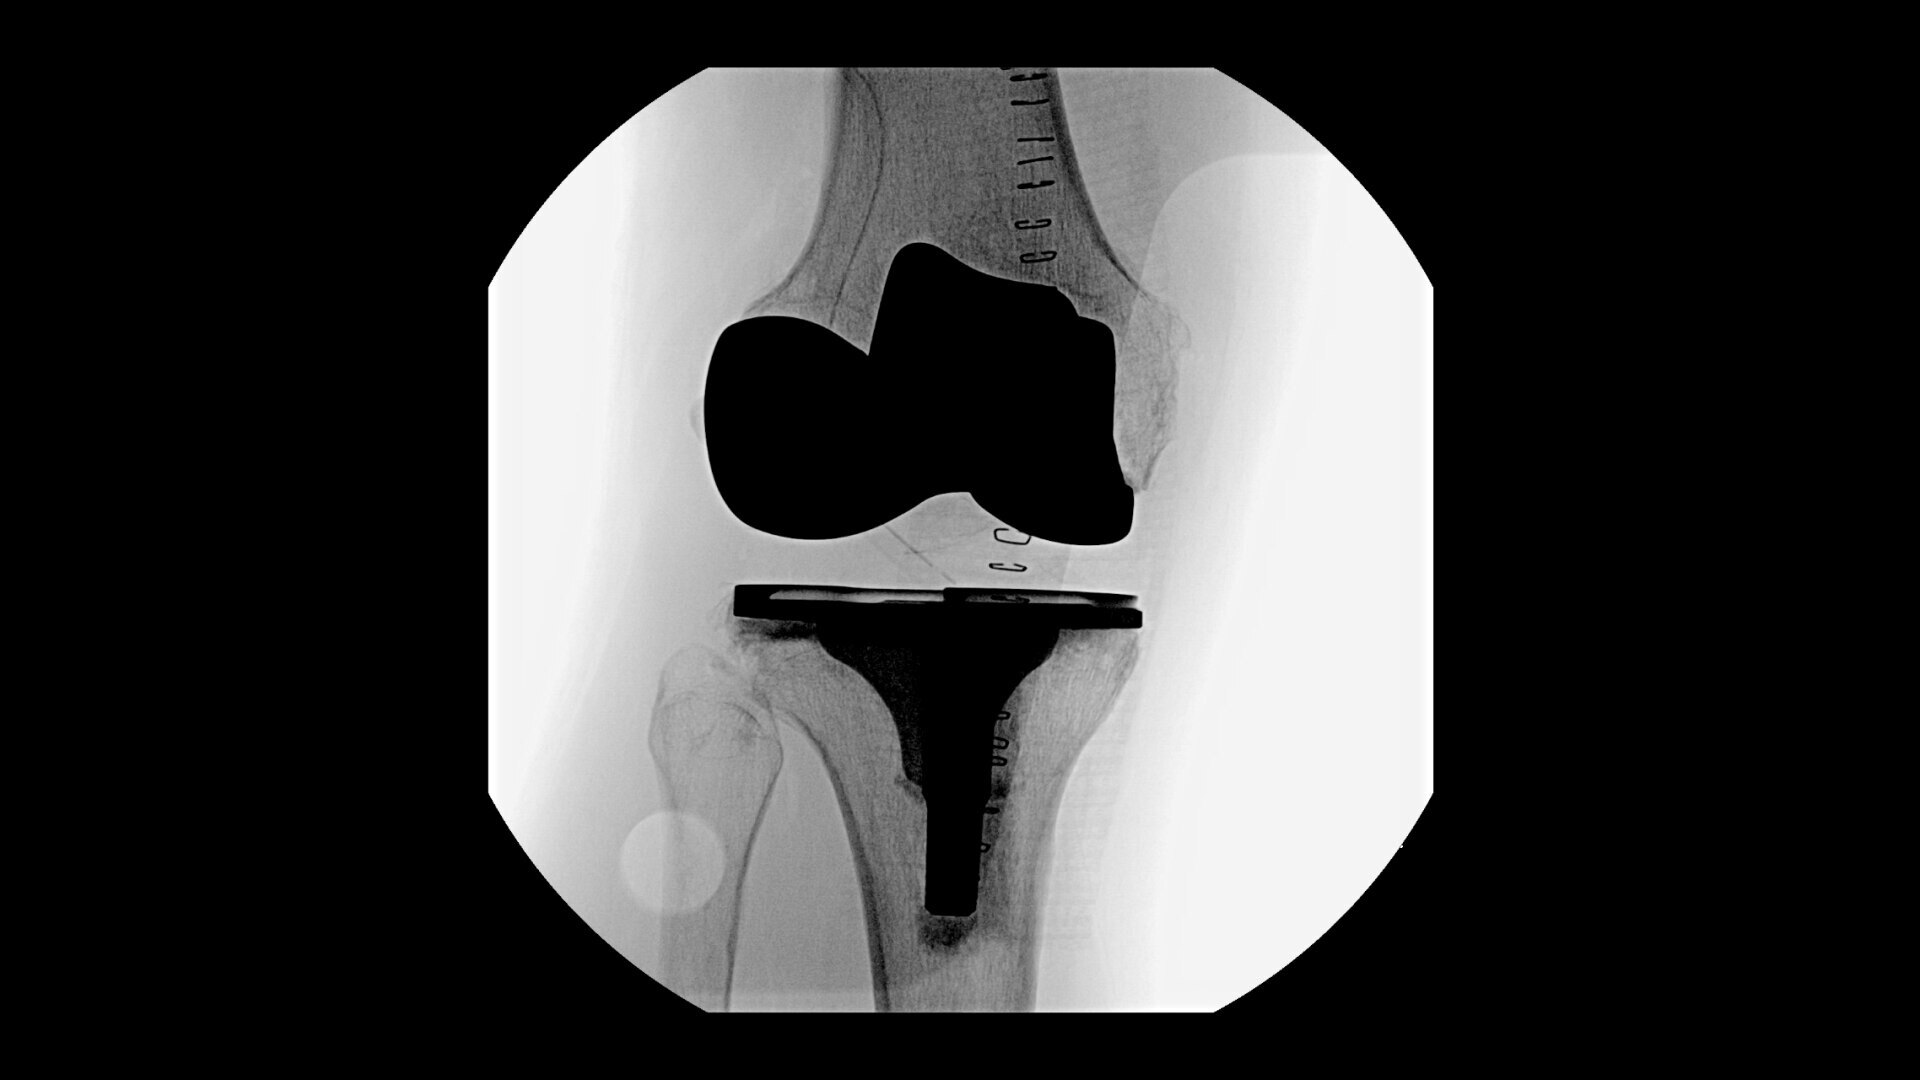

OEC C-arms provide orthopedic imaging with a large field of view optimized to clearly visualize orthopedic anatomy, such as the entire long bone femur or minute fractures in extremities. A clear display with comfortable viewing can easily show AP and lateral views, enabling efficient procedure planning.

See precise anatomical detail of varying densities such as bone and soft tissue with a high dynamic range with the OEC Elite CFD with a flat detector, image processing advancements and 4K viewing display.

Complex orthopedic procedures require powerful imaging systems. OEC premium C-arms perform in a variety of procedures such as:

• Knee replacement